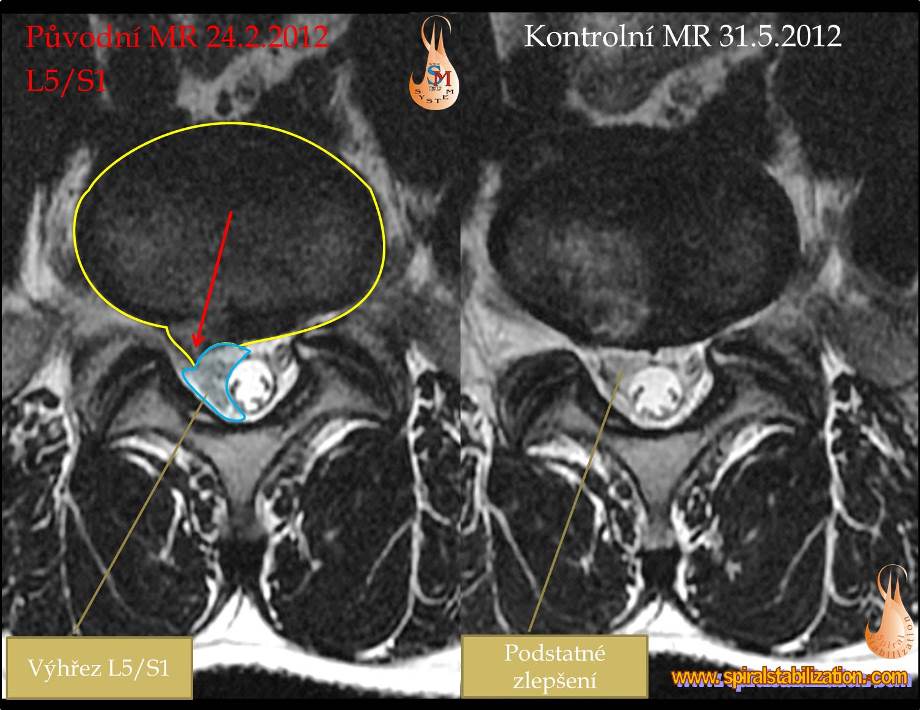

Výsledky hernia L5/S1